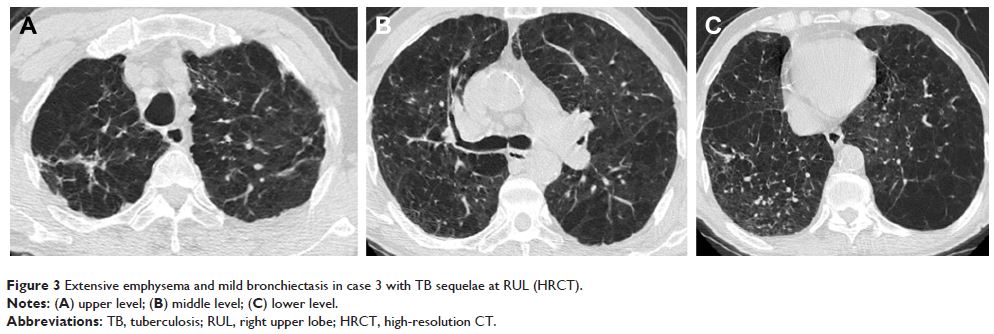

- 作者:Jianmin Jin, Shuling Li, Wenling Yu, Xiaofang Liu, Yongchang Sun

- 期刊:International Journal of Chronic Obstructive Pulmonary Disease